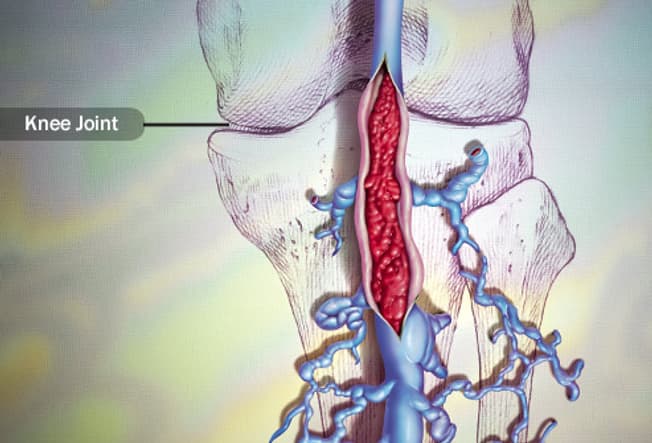

Deep Vein Thrombosis (DVT)

It’s a blood clot that forms in a deep vein, usually in your leg. You can get a DVT if you’ve been on bedrest after illness or surgery, or if you sit for a long time in a plane or car. Lying or sitting for many hours slows your blood flow. Pooled blood can clump together and form clots. The risk with DVT is that a clot could break free and travel to your lungs.